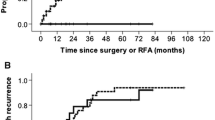

Tumor Progression and Seeding

The median follow-up period was 30.5 months [range 1–97]. LTP was detected in 5/59 tumors (8.5%) with a median time to LTP of 15 months [range 11–42]. By adding one case of NTMBP-RFA primary failure (1.7%), the OLTP rate was 10.2% (6/59 tumors). The 1, 2 and 3-year OLTPFS rates were 98%, 94% and 91%, respectively (Fig. 4). After univariate analysis, no specific factor was associated with OLTP (Table 3). No cases of parietal or peritoneal tumor seeding were observed during follow-up.

DTP occurred in 31/58 patients (53.4%) during follow-up, with a median time to DTP of 15 months [range 1–65]. By adding cases of LTP and DTP, OTPFS rates, therefore, reached 77%, 58% and 44% at 1, 2 and 3 years, respectively (Online resource 1). Univariate analysis did not reveal any factors as being linked with OTP (Online resource 2).

During follow-up, 28/58 patients died (48.2%), two patients were transplanted (3.4%) and two patients (3.4%) were lost to follow-up after 1 and 19 months. The 1, 2 and 3-year OS rates determined using the Kaplan–Meier method were 86%, 73% and 62%, respectively (Online resource 3). After univariate analysis, the exophytic growth of the tumor was the only factor significantly associated with the overall survival (HR 2.96 [1.308–6.709]; P < 0.01) (Online resource 4).